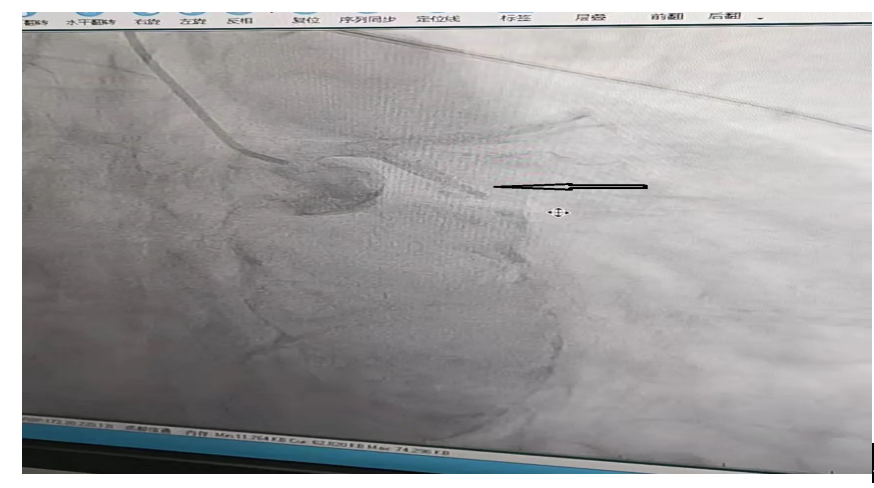

术中,先送入球囊扩张闭塞的回旋支,再冠脉内给予普佑克20mg(溶栓药)溶栓,闭塞的血管开通,血流完全恢复。把患者成功从死亡线上拉了回来。

溶栓后